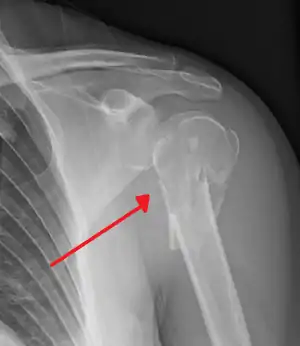

Fracture of the proximal humerus